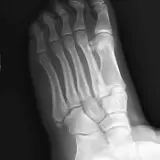

PACSで期待されるツールを完備した完全インタラクティブな症例 — スクロール、ウィンドウ調整、ズーム、パン、計測、ROI、フルスクリーンモード。

重要な所見を症例画像上に直接ハイライトする豊富なアノテーション。症例解説内のリンクされた所見をクリックすると、スキャン上の正確な位置へジャンプできます。

アノテーション付きの画像所見とイラストで効率的に学習